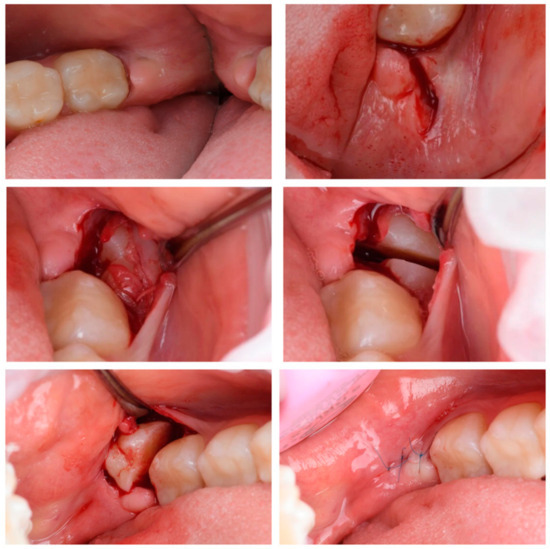

2.2.2. Traditional Method of Third Molar Extraction

Patients in study group 1 with diagnoses of retained teeth (K01.0), impacted teeth (K01.1), chronic apical periodontitis (K04.5), and cementum caries (K02.2) had their lower third molars extracted using cutting instruments and a rotary instrument group (Figure 3). Under local anesthesia with Sol. Ultracaini DS Forte 1:100,000, a 15C scalpel was used to make an incision, and a mucosal–adcostal L-shaped flap was peeled off in the area of the retained mandibular third molar. Using a turbine handpiece, a Lindemann surgical bur, elevators and luxators, the third molar was extracted. Afterwards, we performed a revision of the extracted tooth, control of the integrity of the cavity walls, and hemostasis. The flap was mobilized, placed in the initial position, and the wound was sutured with simple knotted sutures using non-resorbable monofilament suture material: polypropylene 5/0.

Figure 3. Traditional method of third molar extraction.